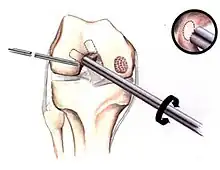

Arthroscopic image of OATS surgery on the medial femoral condyle of the knee

The choice of surgical versus non-surgical treatments for osteochondritis dissecans is controversial.[51] Consequently, the type and extent of surgery necessary varies based on patient age, severity of the lesion, and personal bias of the treating surgeon—entailing an exhaustive list of suggested treatments. A variety of surgical options exist for the treatment of persistently symptomatic, intact, partially detached, and completely detached OCD lesions. Post-surgery reparative cartilage is inferior to healthy hyaline cartilage in glycosaminoglycan concentration, histological, and immunohistochemical appearance.[52] As a result, surgery is often avoided if non-operative treatment is viable.

Intact lesions

If non-surgical measures are unsuccessful, drilling may be considered to stimulate healing of the subchondral bone. Arthroscopic drilling may be performed by using an antegrade (from the front) approach from the joint space through the articular cartilage, or by using a retrograde (from behind) approach through the bone outside of the joint to avoid penetration of the articular cartilage. This has proven successful with positive results at one-year follow-up with antegrade drilling in nine out of eleven teenagers with the juvenile form of OCD,[53] and in 18 of 20 skeletally immature people (follow-up of five years) who had failed prior conservative programs.[54]